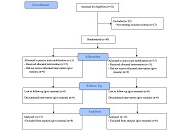

Assessment of CD4+ T cell recovery after direct-acting antiviral hepatitis C treatment in HIV/HCV coinfected immunological nonresponders to ARTOpen AccessOriginal ArticleAim: This study investigated the effects of successful hepatitis C virus (HCV) treatment with direct-acting antivirals (DAAs) on CD4+ T cell recovery in HIV/HCV coinfected immunological non-respo [...] Read more.Violetta Vlasova ... Konstantin ShmagelPublished: May 21, 2025 Explor Med. 2025;6:1001323

Assessment of CD4+ T cell recovery after direct-acting antiviral hepatitis C treatment in HIV/HCV coinfected immunological nonresponders to ARTOpen AccessOriginal ArticleAim: This study investigated the effects of successful hepatitis C virus (HCV) treatment with direct-acting antivirals (DAAs) on CD4+ T cell recovery in HIV/HCV coinfected immunological non-respo [...] Read more.Violetta Vlasova ... Konstantin ShmagelPublished: May 21, 2025 Explor Med. 2025;6:1001323

DOI: https://doi.org/10.37349/emed.2025.1001323